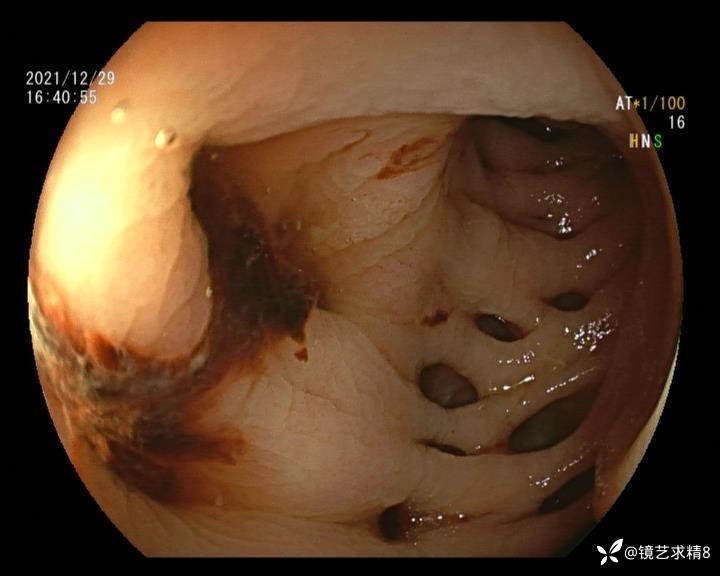

结肠内违建⥤结肠多发憩室☞续

患者以消化道出血入院,胃镜未见异常,肠镜进入乙状结肠就看到很多憩室,同时还看到肠腔用清肠药后移动下来1枚尖锐的枣核,这么多憩室,这个枣核扎入憩室的机会非常大,推测应该是掉入一坑🕳就算出来还会有很多坑🕳🕳🕳等着,掉入憩室内很容易刺破血管,这可能就是消化道出血的原因,继续前进可以看到有一些憩室内翻,还有一些息肉,问题来了,那么多憩室,犯罪分子是抓住了,它在那些憩室内作过案?到达回盲部后挨个冲洗,但憩室大小又不足以把镜头进入憩室内观察,针对有血块的憩室冲洗后可疑出血的以夹子闭合或套扎,取出枣核,如果有锥形透明帽可能钻入憩室精准电凝效果更好,若内镜下操作失败介入治疗成功率更高,经内镜下治疗后观察未再出血出院。

目前研究认为,憩室出血与憩室内血管分布及走行有关。位于憩室颈部或基底部的局部动脉血管仅靠黏膜层与肠腔相隔,随着动脉本身退化或机械损伤,可破裂进入肠腔。值得注意的是,憩室出血通常与炎症无关,憩室炎很少发生明显的出血。